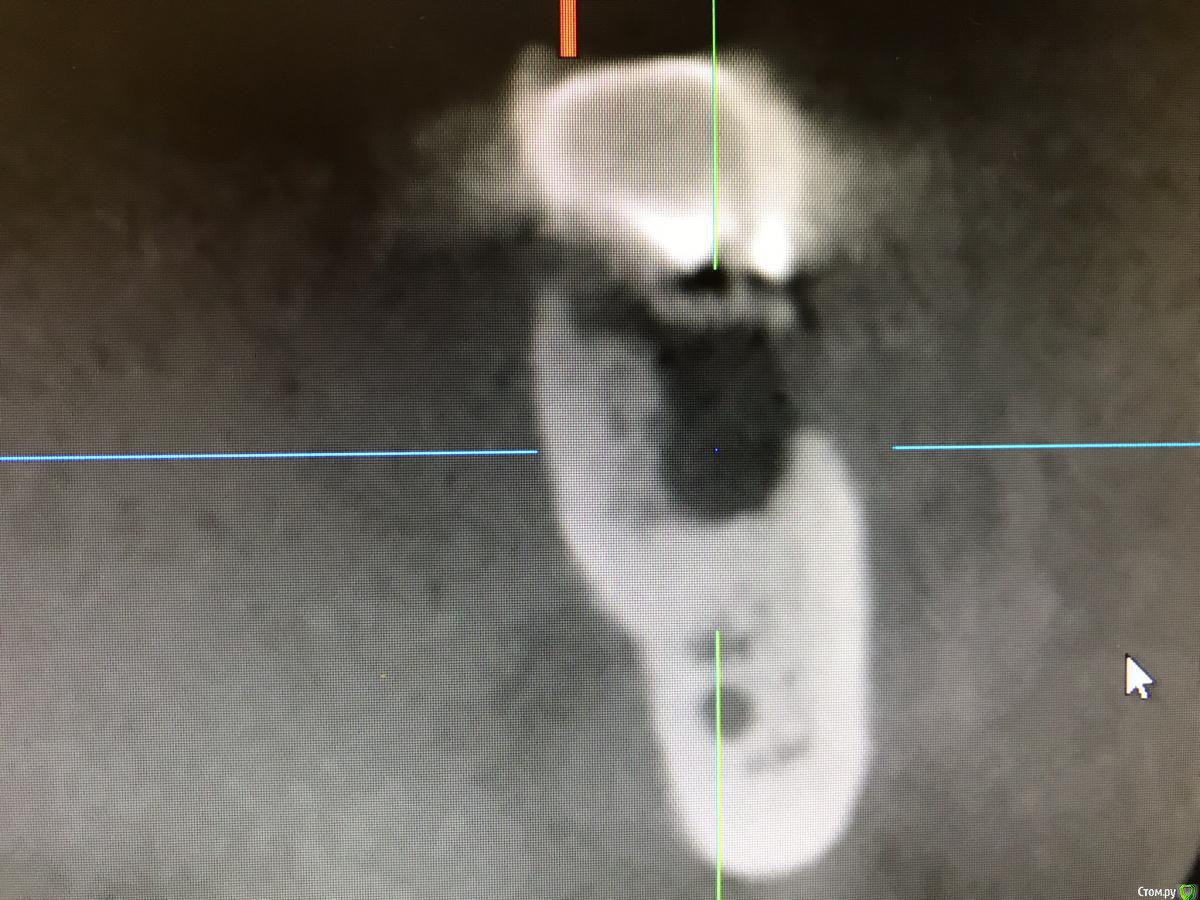

колесников Опубликовано 22 апреля, 2019 Поделиться Опубликовано 22 апреля, 2019 (изменено) И снова профайл спасает жизнь (облегчает жизнь имплантолога)Стандартная ситуация:36 периодонтит в стадии обострения с грануляциями,эксудацией,резорбцией компактной пластинки,дефицитом прикреплённой слизистой вестибулярного. Одна хирургия. Ноябрь 2018. Удаление,кюретаж,имплант Astra tech profile 4.5x9 под заглушку,торк около нуля. Вестибулярного сст,консервация графтом Sureoss 0,5 чипс с APRF,закрытие шайбой по Ноймайеру. Через неделю шайба несостоятельна-удалена. Пациентка созрела на удаление 37го. Выполнена декоронация в связи с отъездом пациентки,далее через 2 недели удаление и имплантация 37го. Промежуточный осмотр в январе. В марте установлены формирователи . Апрель контрольный осмотр. Периотест -5. Направлена на протезирование. Изменено 22 апреля, 2019 пользователем колесников 4 Ссылка на комментарий

колесников Опубликовано 23 апреля, 2019 Автор Поделиться Опубликовано 23 апреля, 2019 Разница от платформы до зенита 3 мм.Ещё раз. Вестибулярно дефект 9мм. Полное отсутсвие прикреплённой слизистой,язычное поднутрение и воспалительный процесс. Чтобы провести олномоментную имплантацию пришлось бы взять короткий имплант,заглубить его на 8мм от зенита,засыпать графтом,перекрыть мембраной,натянуть щеку и ждать-молиться чтобы края не разошлись и все не стухло. А после 2 -3 десневые пластики и глубокая шахта. Господа! Коллеги! Где сроки? Где бюджет? Где прогнозы? Ладно имплант и его глубина, это не так существенно,я вам показал как из ничего за 1 визит получить кератинизированую и прикрепленную слизистую без основания Ссылка на комментарий